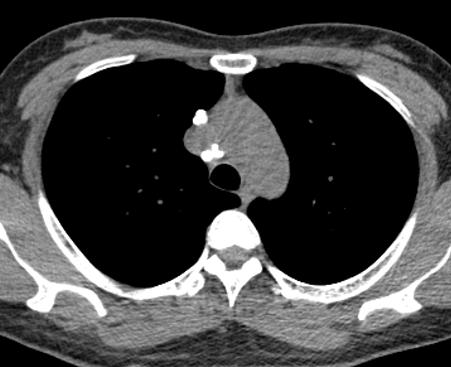

肺部钙化灶脱落,掉进左主支气管(图8),因为钙化病灶是坚硬的、锐利的,就像一个石头在不断地刺激支气管粘膜,导致患者咳嗽。

图8 胸部CT

右中间支气管的钙化病灶向外移动,钙化病灶的尖端刺激到支气管粘膜了(图16)。

图16 胸部CT

另外,这个患者的钙化灶非常危险,因为钙化灶的一端距离肺动脉才2毫米左右(图17),支气管镜下强行牵拉钙化病灶很可能会大出血危及生命。

图17 胸部CT